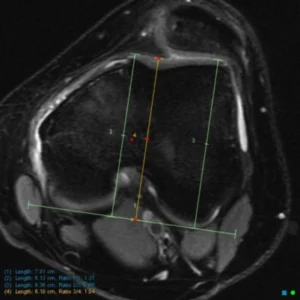

Valutazione dei parametri anatomici

Attraverso l’imaging, in particolare RM e TC nei casi selezionati, è possibile misurare parametri chiave nella valutazione dell’instabilità rotulea, tra cui:

- altezza rotulea

- distanza tibial tuberosity–trochlear groove (TT–TG)

- profondità e forma della troclea femorale

- allineamento complessivo dell’arto inferiore

Questi parametri consentono di distinguere le forme prevalentemente traumatiche da quelle a base costituzionale e di pianificare eventuali trattamenti chirurgici correttivi.